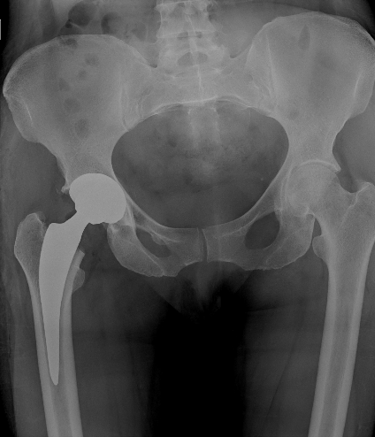

Soy médico cirujano especializado en ortopedia; con una segunda especialidad en cirugía de cadera y preservación articular; enfocado en técnicas mínimamente invasivas, reconstrucción y preservación articular atención personalizada para la preservación articular en pacientes jóvenes y adultos.